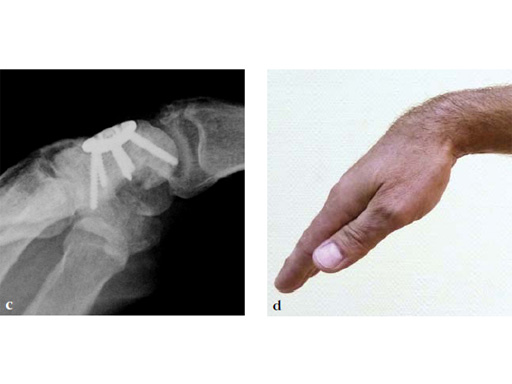

Fig 2ab Dorsal intercalated segment instability correction and K-wire fixation.

Fig 3ab Bone debridement. Guide positioning and fixation.

Fig 3c Bone debridement. Guide positioning and fixation.

Fig 4c Once the carpal junctions have been putting closer by the new reduction-compression guide, reaming is done.